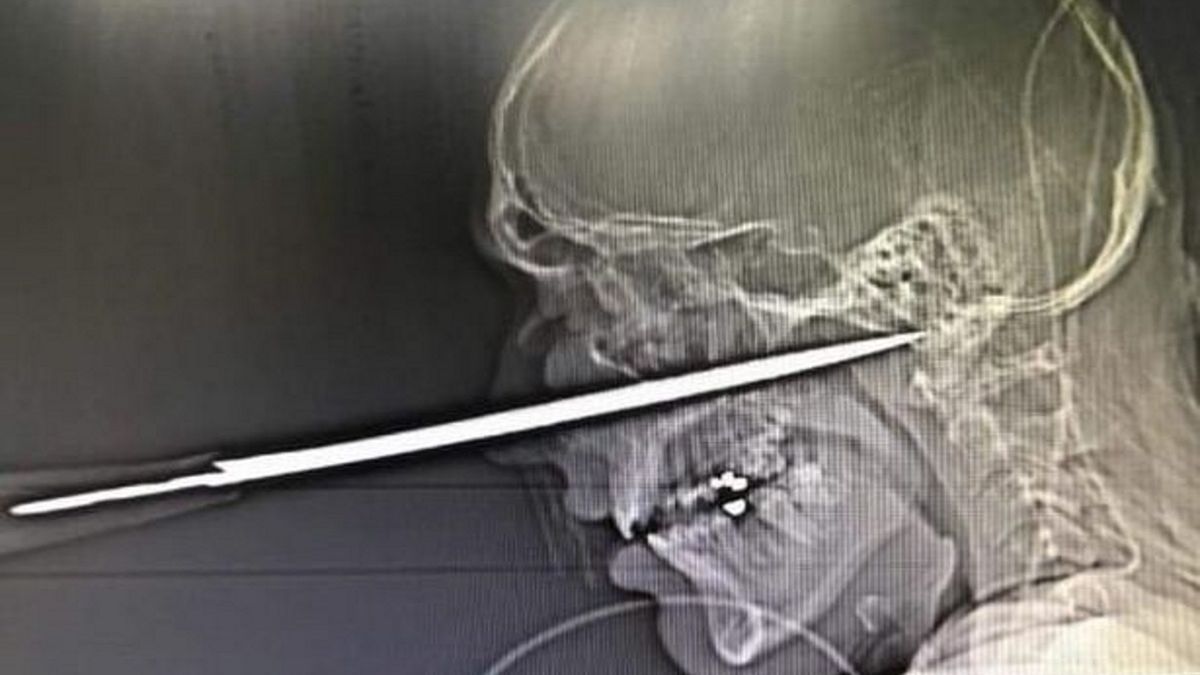

Robbie Pattinson, 21-letni angielski bokser amator, został ciężko ranny w trakcie bójki w pubie. Napastnik wbił mu w twarz nóż kuchenny. Gdyby ostrze wsunęło się o milimetr dalej, młody mężczyzna nie przeżyłby ataku.

Ostrze, które napastnik wbił 21-latkowi w twarz, mierzyło kilkanaście centymetrów. Lekarze stwierdzili, że bokserowi udało się uniknąć śmierci, ponieważ nóż ominął główną tętnicę. Od wykrwawienia i pewnej śmierci Pattinsona dzielił zaledwie milimetr.